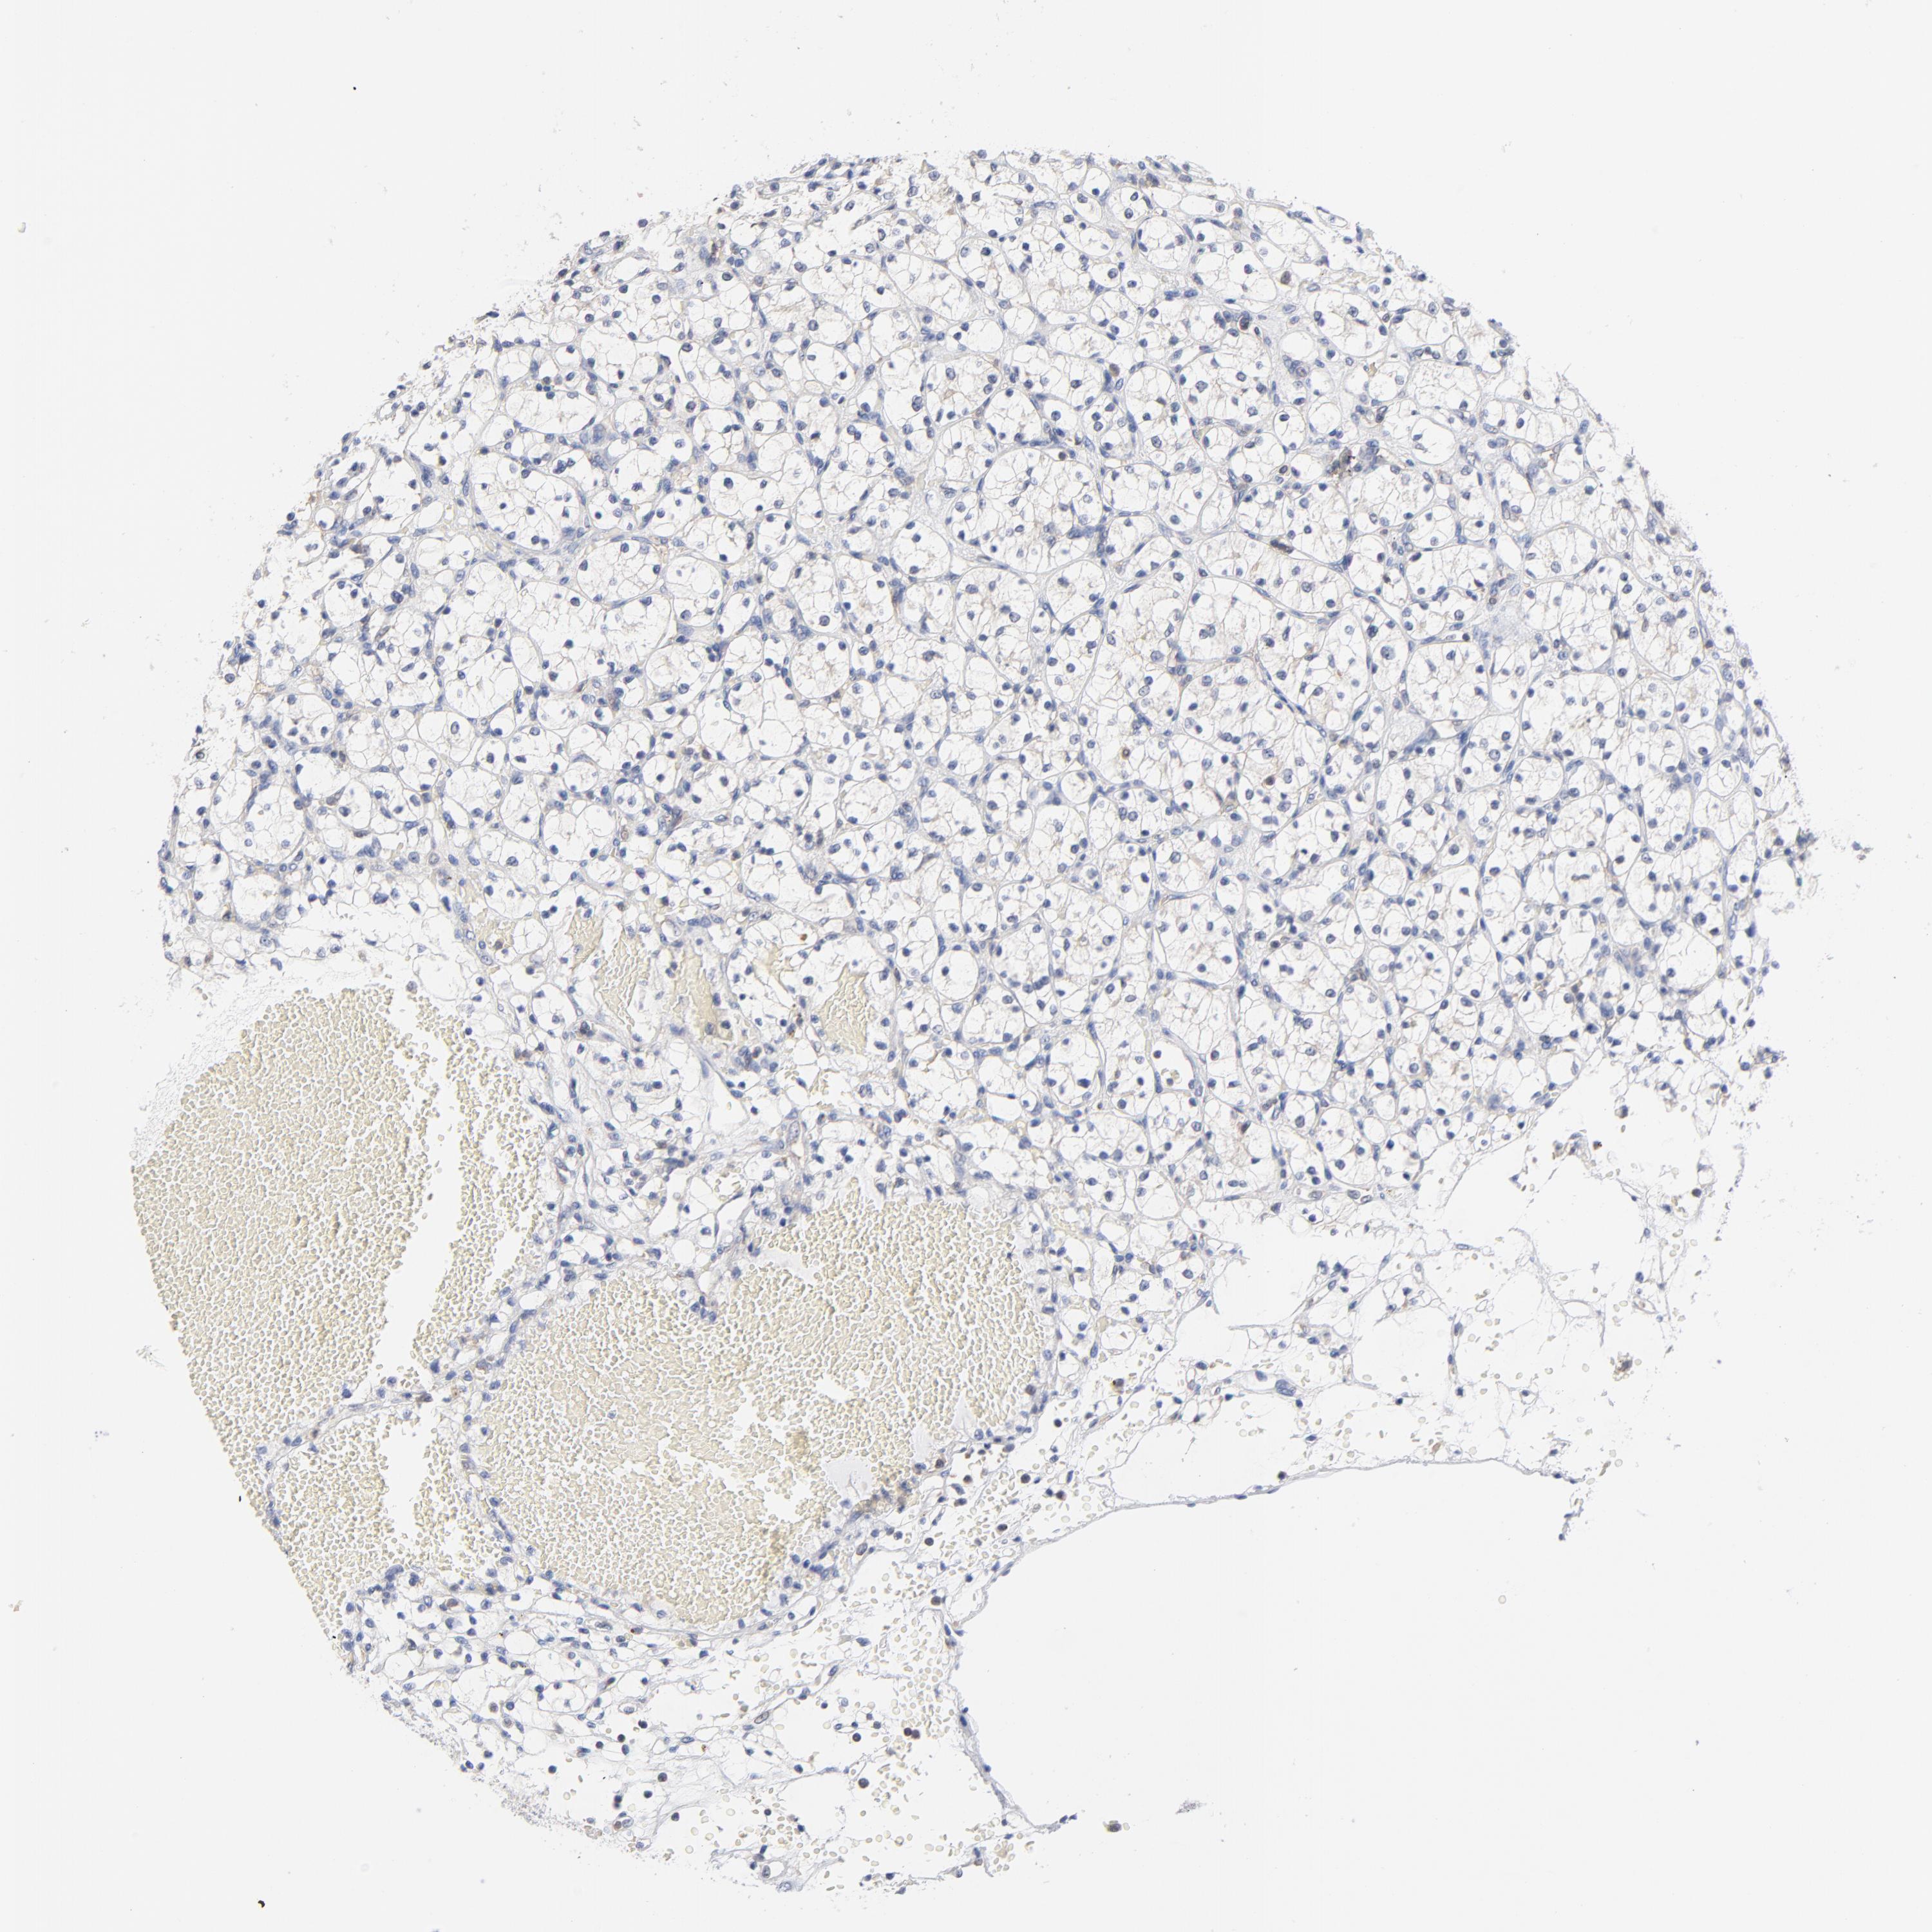

KIDNEY RENAL CLEAR CELL CARCINOMA (VALIDATION) - Interactive survival scatter ploti

The Survival Scatter plot shows the clinical status (i.e. dead or alive) for all individuals in the patient cohort, based on the same data that underlies the corresponding Kaplan-Meier plots. Patients that are alive at last time for follow-up are shown in blue and patients who have died during the study are shown in red.

The x-axis shows the expression levels (FPKM) of the investigated gene in the tumor tissue at the time of diagnosis. The y-axis shows the follow-up time after diagnosis (years). Both axes are complimented with kernel density curves demonstrating the data density over the axes. The top density plot shows the expression levels (FPKM) distribution among dead (red) and alive patients (blue). The right density plot shows the data density of the survived years of dead patients with high and low expression levels respectively, stratified using the cutoff indicated by the vertical dashed line through the Survival Scatter plot. This cutoff is automatically defined based on the FPKM cutoff that minimizes the p-score. The cutoff can be changed by dragging the vertical line or by entering a cutoff value in the square labeled "Current cut-off".

Under the Survival Scatter plot the p-score landscape (black curve; left axis) is shown together with dead median separation (red curve; right axis). Dead median separation is the difference in median mRNA expression between patients who have died with high and low expression, respectively. It is calculated as follows: median FPKM expression of dead patients with high expression - median FPKM expression of dead patients with low expression. This is intended to aid the user in visually exploring custom cutoffs and the associated p-scores and dead median separation.

Individual patient data is displayed and can be filtered by clicking on one or more of the category buttons on the top of the page. Categories describing expression level and patient information include: high, low, alive, dead, female, male and tumor stages. The scale of the x-axis can be toggled between linear and log-scale by clicking on the "x log" button. Mouse-over function shows TCGA ID, patient information and mRNA expression (FPKM) for each patient.

& Survival analysisi

Kaplan-Meier plots summarize results from analysis of correlation between mRNA expression level and patient survival. Patients were divided based on level of expression into one of the two groups "low" (under cut off) or "high" (over cut off). X-axis shows time for survival (years) and y-axis shows the probability of survival, where 1.0 corresponds to 100 percent.

CAB39L is not prognostic in Kidney Renal Clear Cell Carcinoma (validation)

Best expression cut offi

Based on the FPKM value of each gene, patients were classified into two groups and association between prognosis (survival) and gene expression (FPKM) was examined. The best expression cut-off refers the FPKM value that yields maximal difference with regard to survival between the two groups at the lowest log-rank P-value. Best expression cut-off was selected based on survival analysis .

When clicking on this number, the vertical dashed line indicating cut-off, the interactive survival plot, and the Kaplan-Meier curve will be adjusted to show results based on the best expression cut-off.

: 6.59

TCGA RNA samplesi

RNA-seq data is reported as average FPKM (number Fragments Per Kilobase of exon per Million reads), generated by the The Cancer Genome Atlas (TCGA) .

Normal distribution across the dataset is visualized with box plots, shown as median and 25th and 75th percentiles. Points are displayed as outliers if they are above or below 1.5 times the interquartile range. FPKM values of the individual samples are presented next to the box plot.

Average pTPM 6.8

Number of samples 100